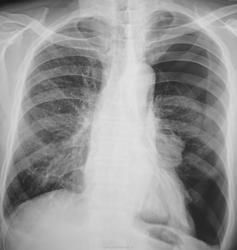

Левосторонний пневмоторакс. Ателектаз левого лёгкого.

Ребра  вроде бы целы. Пациент, насколько вижу, астеник. Булла рванула?

Булла - наиболее вероятна. Она каааааааааак рванёт!!!

Но кровь в синусах есть.

Травмы не было. Пациент направлен врачом общей практики с диагнозом... - "Пнемония"....

Заболел почти внезапно.

Вуаля! Так оно обычно и бывает. Знакомый мой один, к примеру, перетаскивал тяжелую лестницу, как вдруг... острая боль в боку, одышка, ну а дальше все по схеме (знакомый, кстати, молодой астеник). На R-граммах субтотальный пневмоторакс, на КТ после дренирования множественные разнокалиберные тонкостенные буллы в верхушках обоих легких. Здесь, вероятно, было бы тоже самое.

Колабирование - да!, а ателектаз ли?